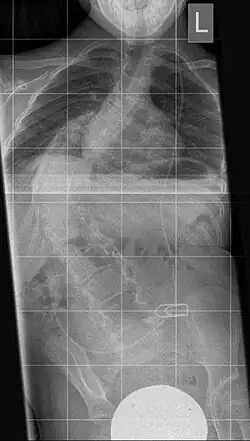

The instrument is used to dilate a too small or too narrow rib thorax in severe thoracic deformity. It consists of a telescopic "titanium rib" in curved form with several holes in a row for fixing in the desired length. A prolongation can be carried out after 6 months. The fixation takes place between two ribs or between a rib and the iliac crest. This results in an indirect erection of the deformed spine, resulting in an increase in the volume of the thoracic cavity along with the lung.